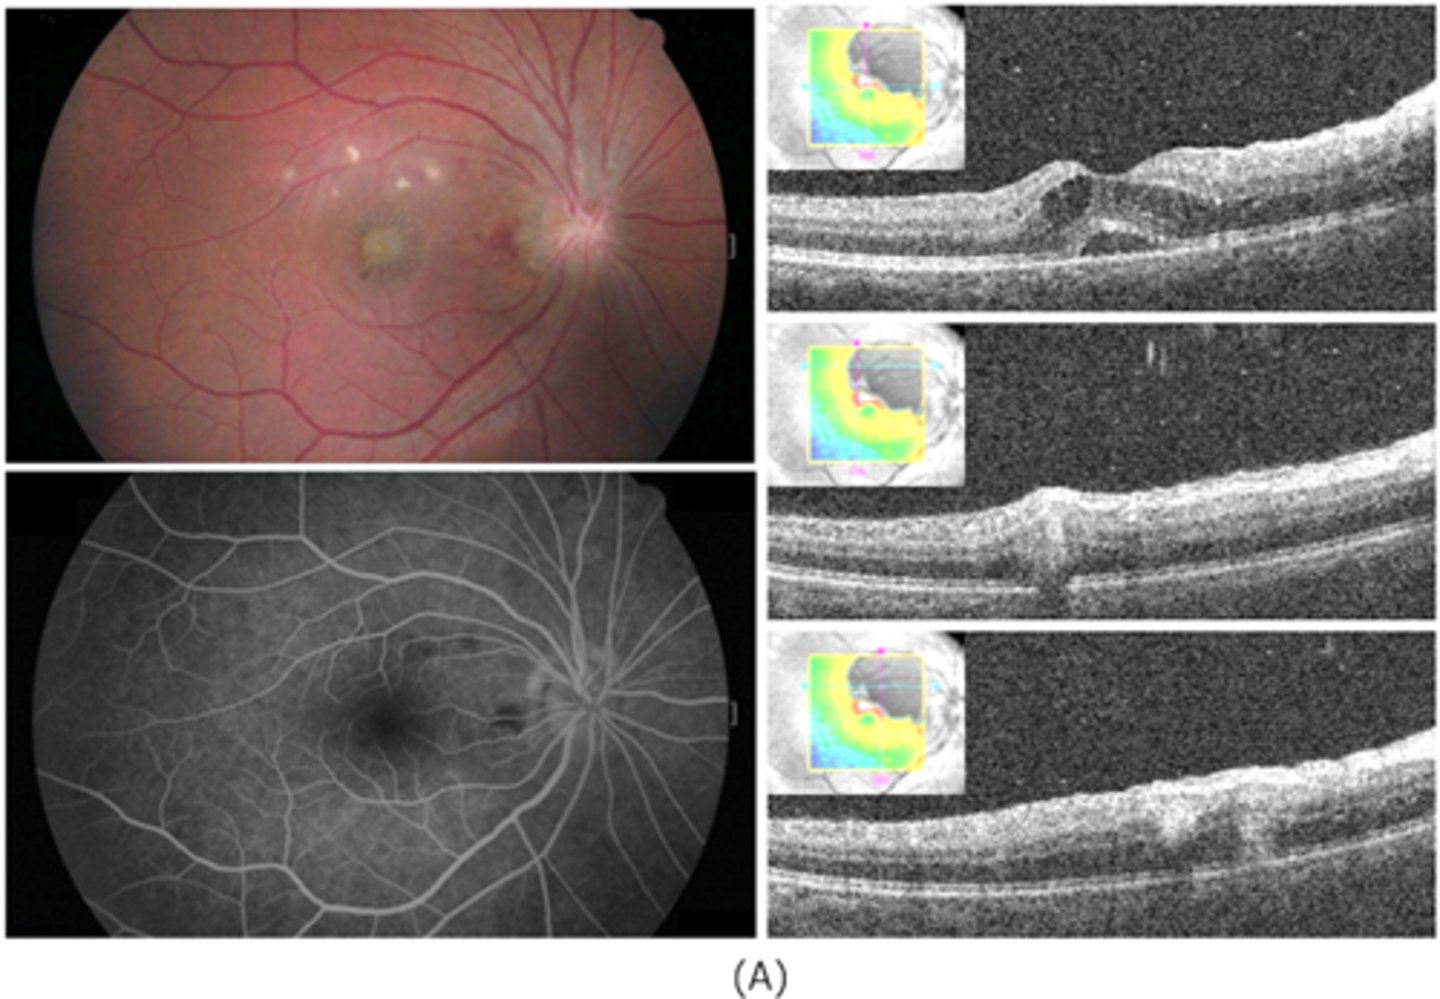

What causes ocular toxocariasis?

nematode roundworms in dogs and cats (Toxocara canis or Toxocara cati) = live in dog/cat stomach and release eggs in stool that enters soil, causing...

visceral larva migrans (VLM) = systemic

ocular larva migrans (OLM) = posterior uveitis

What are 3 subtypes of ocular toxocariasis?

central posterior granuloma

peripheral granuloma

chronic endophthalmitis

What are some signs of ocular toxocariasis?

UNILATERAL

granuloma = hazy white lesion made up of inflam debris

vitritis that can mimic endophthalmitis

fibrocellular stalks made up of inflam debris can contract = tugs on retina = retinal folds

NO chorioretinal scar

How does ocular toxocariasis appear on OCT, as seen here in patient A?

multiple light granulomas = hyperR

How does ocular toxocariasis appear on OCT, as seen here in patient B?

recurrence = granulomas with exudates, edema

How does ocular toxocariasis appear on OCT, as seen here in patient C?

granuloma now in nasal retina, fibrous memb where granuloma once was (looks like ERM)

How does ocular toxocariasis appear on B-scan here?

granuloma mass over ONH = high-reflectivity